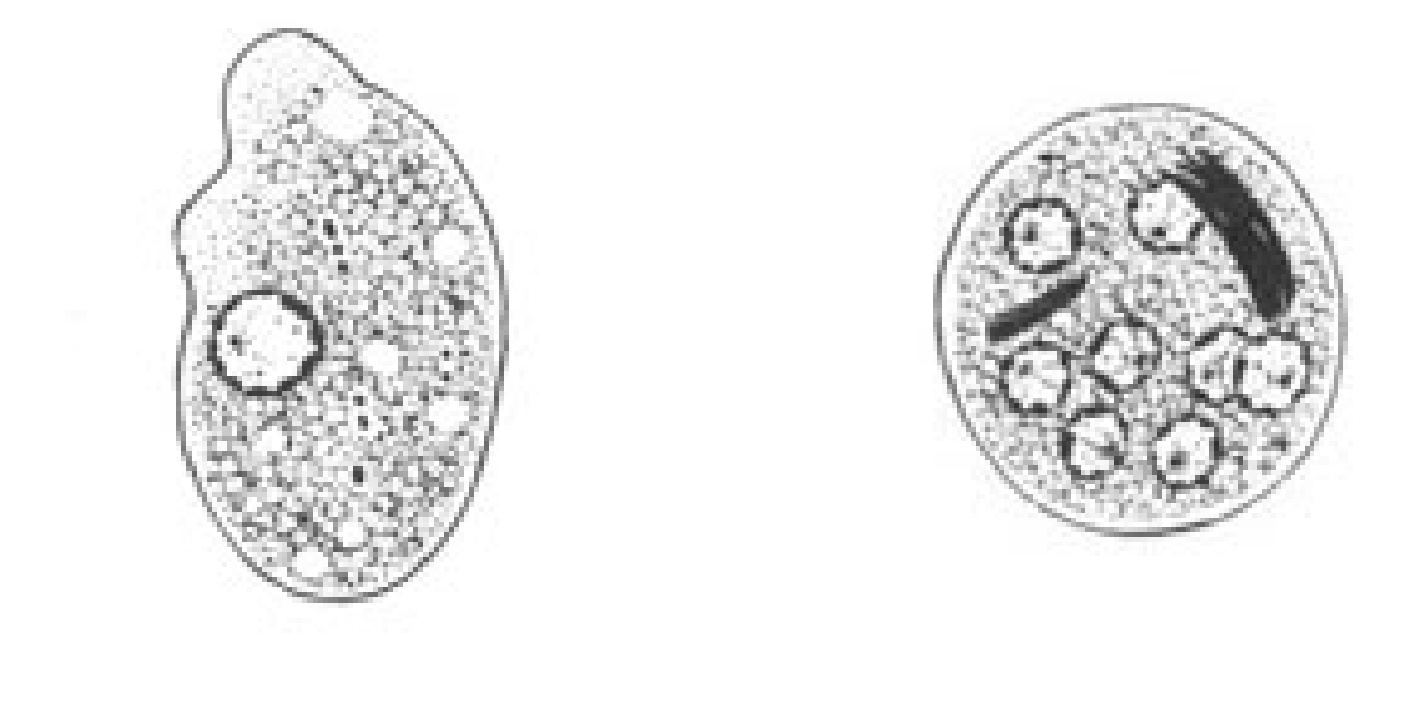

Entamoeba coli

E. coli troph form

E.coli troph form

What parasite has splintered chromatoidal bars and may contain glycogen vacuoles and has up to 8 nuclei?

E. coli

E. coli cyst

E.coli cyst